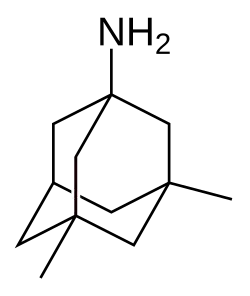

| Medicação | Inibidores da acetilcolinesterase, antagonistas dos recetores de NMDA (poucos benefícios)[6] |

Atualmente são usados cinco medicamentos no tratamento dos problemas cognitivos de Alzheimer: quatro são inibidores da acetilcolinesterase (tacrina, rivastigmina, galantamina e donepezila), sendo o outro um antagonista dos recetores de NMDA (memantina).[169] No entanto, os benefícios da sua utilização são pouco significativos.[170][171]

A diminuição da atividade dos neurónios colinérgicos é uma característica bem compreendida da doença de Alzheimer.[172] Os inibidores da acetilcolinesterase são usados para reduzir a velocidade a que a acetilcolina (ACh) é fragmentada, aumentando assim a concentração de ACh no cérebro e combatendo a perda de ACh provocada pela morte dos neurónios colinérgicos.[173] Existem evidências da eficácia destes medicamentos em casos leves a moderados da doença,[174][175] e algumas evidências durante a fase avançada. Só a donepezila é que está aprovada para o tratamento da demência avançada de Alzheimer.[176] A utilização destes fármacos no défice cognitivo ligeiro não demonstrou ter qualquer efeito no atraso do aparecimento de Alzheimer.[177] As reações adversas mais comuns são náuseas e vómitos, ambos ligados ao excesso colinérgico. Estas reações adversas manifestam-se em cerca de 10-20% dos utilizadores, a sua gravidade é entre leve e moderada e podem ser controladas através do ajuste gradual das doses de medicação.[178] Entre os efeitos secundários menos comuns estão cãibras musculares, diminuição do ritmo cardíaco, diminuição do apetite e do peso e aumento da produção de ácido gástrico.[179]